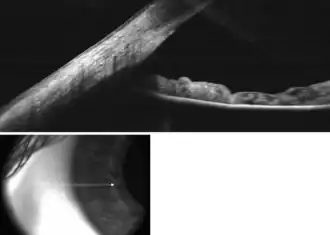

The EZ ratio method is one way to calculate the estimated anterior chamber depth.[2] To start, the patient looks at a target in the distance with one eye covered. The examiner takes a digital photograph of the open, examined eye, from the side, perpendicular to the visual axis (a profile photograph).

The following parameters then need to be measured in the photograph, using a personal computer or a smartphone (figures 1,2):

1. The pixel distance between the limbus (the junction between clear cornea and white sclera) and the front of the cornea. This distance is referred to as Z.

2. The pixel distance between the limbus and the centre of the pupil. This distance is referred to as E.

E:Z ratio is the arithmetic ratio between E and Z.

This ratio is linearly correlated with the depth of the anterior chamber with the following equation:

Anterior chamber depth (expressed in millimetres) = -3.3 x EZ ratio + 4.2

This estimate has been shown to be accurate with a 95% confidence interval of +/– 0.33 mm error, when compared to measurements of the anterior chamber depth by Scheimpflug photography.[2]